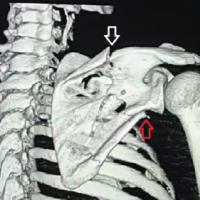

A 50-year-old right-hand dominant male presented to the orthopedic office for evaluation of chronic right elbow pain. He states this has been ongoing since he sustained an injury, while in the military, about 7 years ago. Over this period, he underwent 7 different surgeries related to this injury, with the most recent procedure in January of 2011. He noted considerable pain, stiffness, and significant difficulty performing tasks at work and activities of daily living. His pre-operative Visual Analog Scale (VAS) pain score was a 10 out of 10, mayo elbow performance score (MEPS) was 15/100 (<60 indicating poor performance), American shoulder and elbow surgeons (ASES) score of 18/100, and disabilities of the arm, shoulder and hand (DASH) score of 70/100 with additional noted severe difficulty performing his required work activities as a sports photographer. He also indicated that he was unable to participate in bowling, his sport of most importance, on pre-operative questionnaires. Radiographs and a computed tomography scan were obtained, which demonstrated advanced degenerative changes in the radiocapitellar and ulnohumeral joints (Fig. 1). Given his age, job requirements, and lifestyle, we felt the patient would not be a great candidate for a total elbow replacement given the activity and post-operative weight restrictions. Instead, we recommended treatment with an interpositional arthroplasty for the treatment of his post-traumatic osteoarthritis (Figs. 2 and 3).